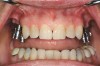

Figure 2  Removable prostheses can provide proper support and enhance overall facial esthetics for the patient.

Figure 2

Figure 3  Removable prostheses can provide proper support and enhance overall facial esthetics for the patient.

Figure 3